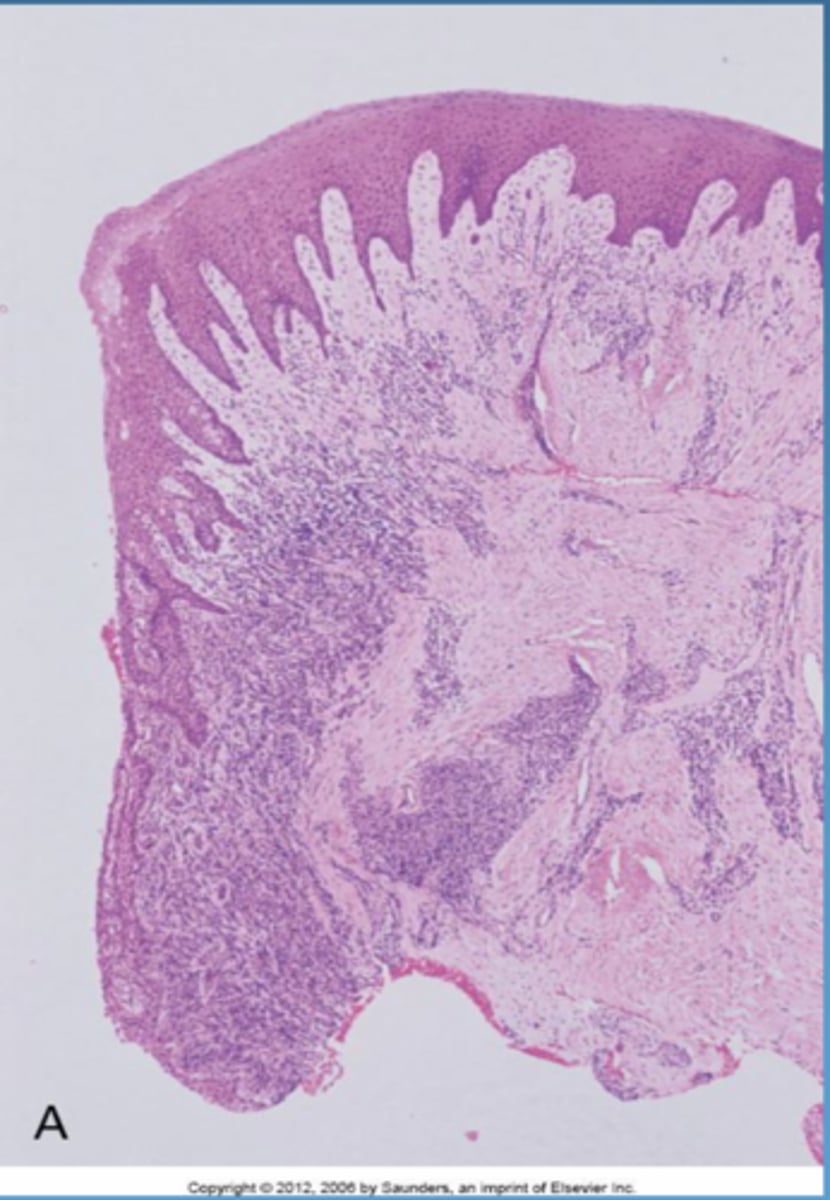

histopathology of gingival disease stages

stage 1 = initial lesion

stage 2 = early lesion

stage 3 = established lesion

stage 4 = advanced lesion

*know what cell present, inflammatory response, and how many days*

histopathology of gingival disease visual

established lesion (14-21 days)

- changes in early lesion worsen

- continued breakdown of collagen, vascular prolfieration, developed/elongated formation of rete pegs

- moderately to severely inflamed gingiva

-changes in color, size, texture, consistency, contour of gingiva

-NO attachment loss

-gingival lesion is reversible

advanced lesion (periodontitis)

- extension of lesion into alveolar bone

- apical migration of junctional epithelium

bone loss:

- RANK/RANKL

-loss of attachment

-clinical signs of acute and/or chronic sings of inflammation may be present

periodontitis visual

-- in 2 diff teeth.. changes are dependent for localized area (site specific)

-- not all pt respond to bacteria same way